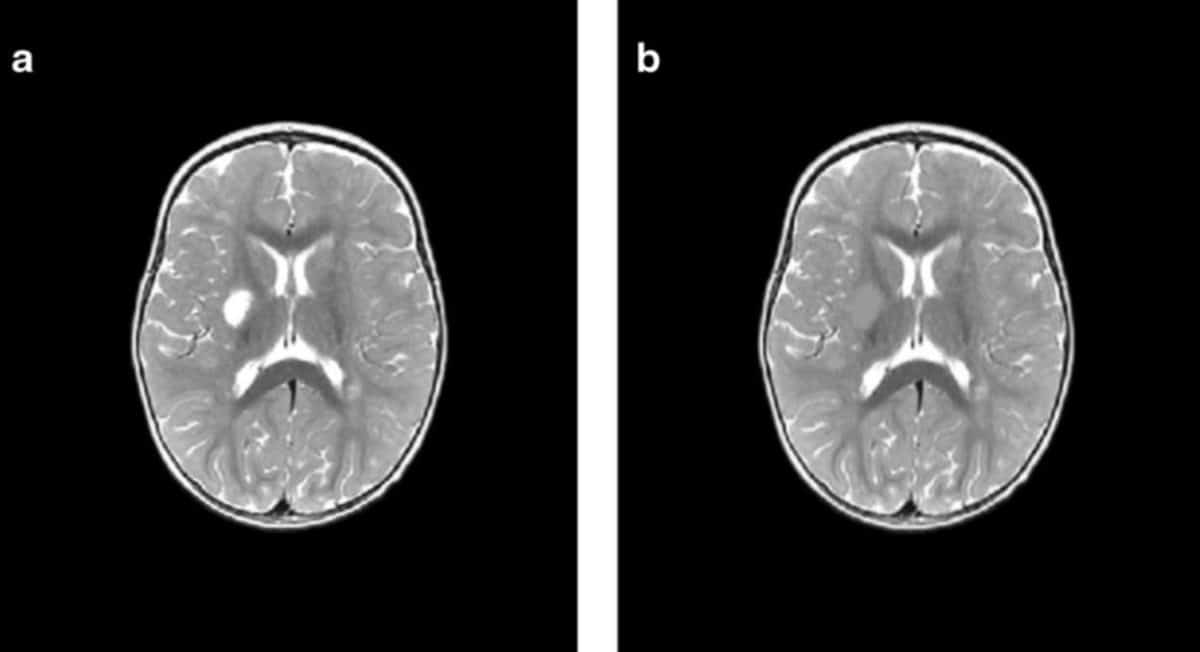

Исследователи проанализировали данные МРТ 35 детей, которые перенесли ишемический инсульт в возрасте до двух лет и лечились в больницах Екатеринбурга, Перми, Челябинска и Тюмени в период с 2015 по 2019 год. Возраст детей на момент инсульта варьировался от четырех дней до одного года 11 месяцев.

Для оценки последствий инсульта исследователи применили современный метод анализа снимков — воксель-базированную морфометрию. Упрощенно эту технологию можно представить так: на каждом МРТ-снимке слой за слоем вручную обводят контуры повреждений области мозга, а специальная компьютерная программа затем вычисляет точный объем этой зоны в кубических миллиметрах. Такая технология позволяет получить наиболее объективные данные по сравнению с традиционным МРТ-отчетом, направленным на определение качественных характеристик (точных границ инсульта, его локализации). Воксель-базированная морфометрия позволяет получить количественные данные: абсолютный и относительный объем поражения от общего объема мозга. Результат применения такого метода — точные числовые значения для последующего статистического анализа и сравнения.

Оказалось, что инсульты у младенцев и детей, достигших месячного возраста, различаются и по масштабам, и по характеру повреждений. Так, у малышей с перинатальным инсультом объем повреждения мозга оказался намного серьезнее, чем у старших: 7,9% против 1,6% от объема мозга. Также у новорожденных чаще встречались нарушения, затрагивающие кору мозга, смешанные и двусторонние инсульты, а у группы детей от 28 дней до двух лет преобладали локальные подкорковые очаги и повреждения только левого полушария.